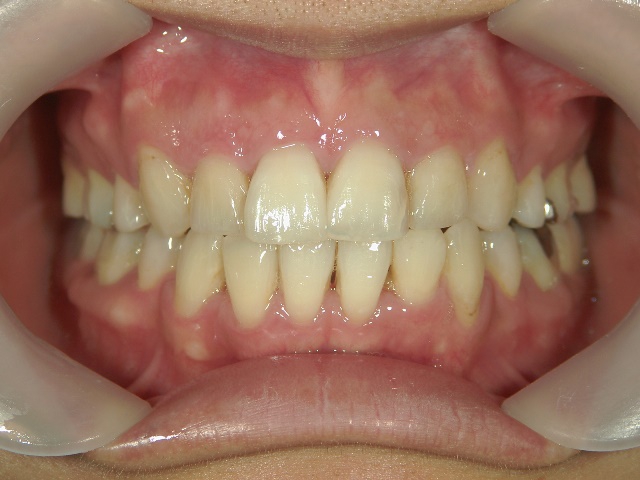

矯正歯科 治療後矯正歯科 全顎ワイヤー矯正 治療後矯正歯科(全顎ワイヤー矯正)治療後

矯正歯科 治療後